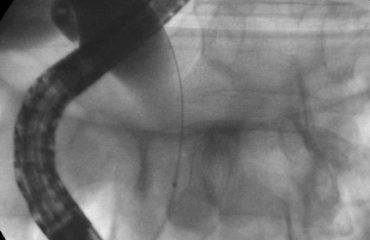

La coloscopie consiste en l’exploration du côlon et du rectum pour détecter des anomalies d’origine cancéreuse ou non. Couramment pratiquée, elle peut être prescrite en cas de symptômes intestinaux non expliqués (douleurs, diarrhées), de saignements intestinaux (traces de sang dans les selles), d’antécédents familiaux ou personnels de cancer colorectal, ainsi que pour toutes personnes de plus de 50 ans sans prédisposition particulière.

Une fois sous anesthésie générale, le coloscope est introduit par l’anus puis progressivement amené jusqu’au côlon. Afin de déplisser les tissus, le côlon est gonflé par de l’air permettant ainsi une bonne visualisation de toutes les parois. Au fur et à mesure de la progression du coloscope, des images sont directement transmises et analysées par le gastroentérologue. Si des anomalies sont détectées, un échantillon de tissu est prélevé pour analyse ultérieure (biopsie). Il est également possible que l’intégralité du tissu anormal soit enlevée (ablation).